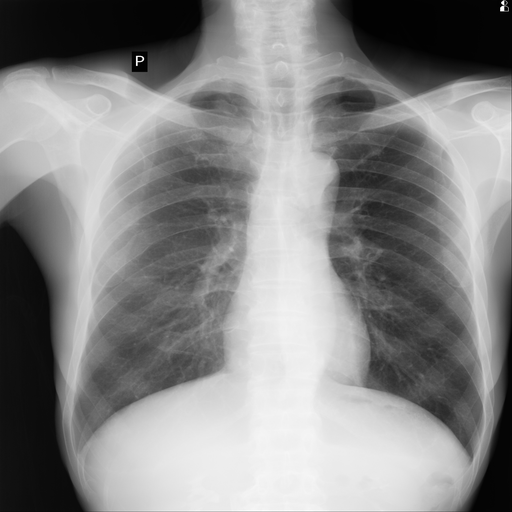

Chest X-Ray Abnormal Detection

Self-supervised anomaly detection for chest radiographs

2.png